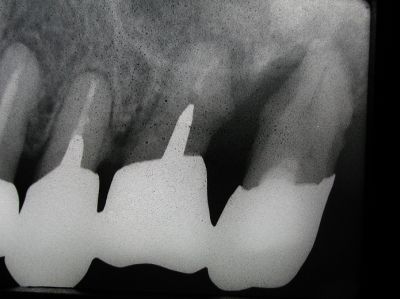

ソフトレーザーまたはYagレーザーとプロポリス(蜂の巣の成分)を使って、骨を再生する画期的な新しい治療方法です。

以下の写真は、歯周病で100%抜歯するしかない歯をプロポリスを使って骨再生した例です。